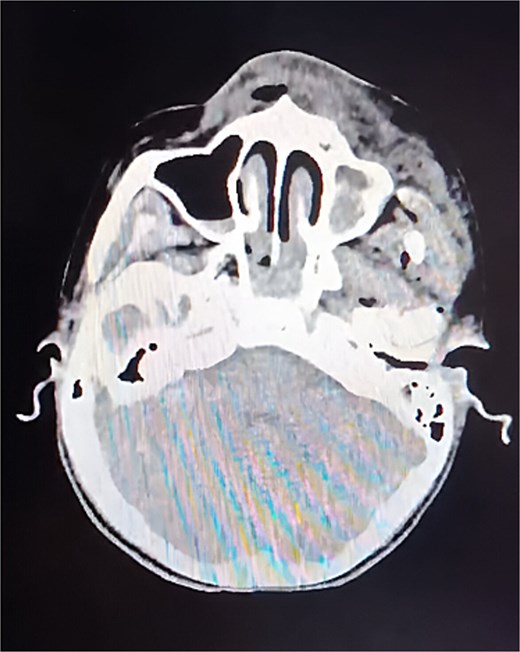

A non-contrast cranial computed tomography (CT) scan (Fig. 1) revealed fractures of the orbital roof, nasal bones, and left zygomatic bone, as well as a frontal fracture, intraparenchymal hemorrhages in the parietal and temporal lobes, and hemorrhage within the paranasal sinuses. Laboratory tests were unremarkable.

CT of the skull, axial slice. A cranial base fracture is evident, with bleeding at the level of the maxillary sinus. Small areas of bleeding are also observed in the intraparenchymal region.